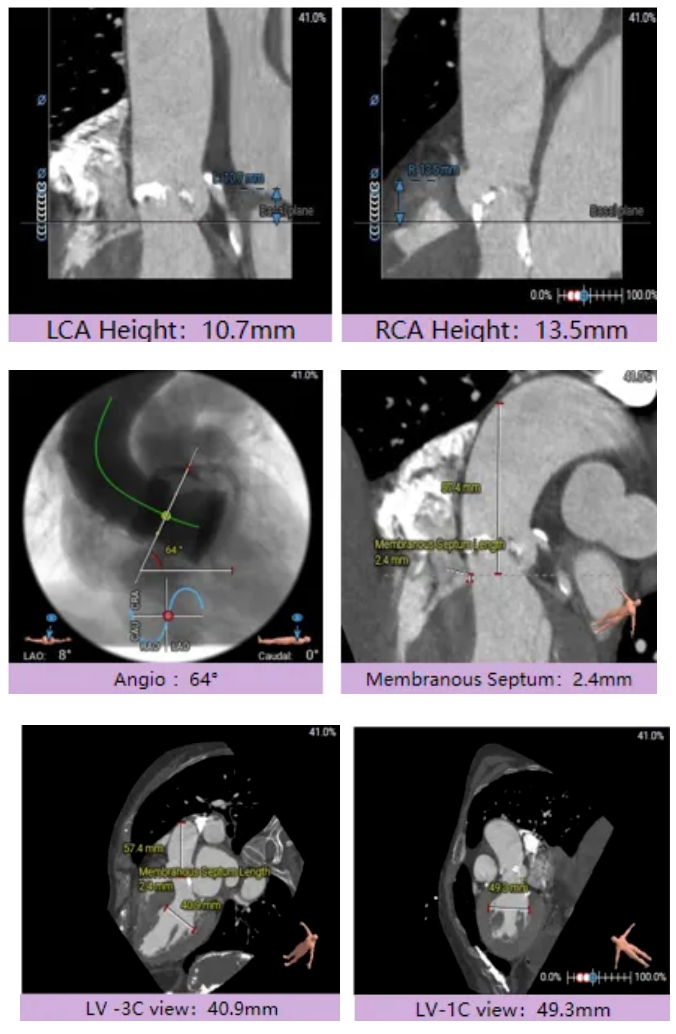

宋光远教授 首都医科大学附属北京安贞医院(点击查看专家详细简历) 技术革新不止,创新求索不辍:一切从患者出发,不断追求创新是内心的坚定。当年‘ALL IN ONE’的探索,正是怀揣着这份初心 —— 通过整合器械与操作,将入路创伤缩至最小,让患者在微创中更快康复,这是技术对患者的温柔承诺。而术中脑保护,是我们为安全筑牢的另一道防线。 此次预装干瓣的临床应用,让我们直面瓣膜“耐久性“临床困境,期待创新技术助力全生命周期管理! 病例概览 患者病史 患者因 “劳力性呼吸困难半年余,加重 20 天” 入院。高血压病史 20 年,最高血压 160/110mmHg;高脂血症病史;反流性食管炎。 超声提示:主动脉流速 Vmax 4.66 m/s,平均压差 53mmHg,左室射血分数(LVEF)40%; 超声诊断:主动脉瓣狭窄(重度)、主动脉瓣反流(轻中度)、二尖瓣狭窄(轻度)、二尖瓣反流(轻度)、三尖瓣反流(轻中度)、左房增大,左室肥厚。 术前CT 瓣环(Annulus)直径:22.9mm,左室流出道(LVOT)直径:周长径 23.8mm;总钙化负荷1239mm³(HU850),钙化集中于无冠窦,且蔓延至 LVOT,呈重度钙化表现;LVOT-Annulus 呈微直筒型,瓣上限制较重。左冠脉开口高度略低,瓣叶不长、窦部空间较大,结合钙化分部情况,预估双侧冠脉遮挡风险较低。室间隔膜部较短(2.4mm)有一定PPI风险,心室大小可,心脏角度64°,升主长度短于胶囊腔长度,同轴有一定困难。 · 造影角度及入路情况:主动脉弓角度可,但降主动脉折曲明显,双侧髂股动脉存在粥样硬化。 手术策略 采用 “极简式” 手术方案:18/20mm 球囊预扩张,植入金仕生物 Prostyle-A 预装干瓣(AV 26),配合长鞘,同时植入脑保护装置以降低卒中风险。 手术过程 球囊预扩:18号球囊预扩 输送系统顺利过弓跨瓣: 瓣膜植入:工作位观察位置适宜,完成植入。 术后即刻:术后造影显示瓣膜位置佳 入路与血管:撤出大鞘后检查,降主动脉仍存在较大弯折;入路闭合良好,无明显出血或血管并发症。 Prostyle A®预装干瓣——助力临床最优化解决方案: √ Mircro-EX™专利抗钙化技术:极简式预装干瓣,不使用戊二醛浸泡,减少钙化成因,干态存储的瓣膜术中无需清洗瓣膜,减少组装步骤,缩短手术时间,尤其适合复杂病例中的高效操作; √ 平衡的径向支撑力:重度钙化的患者,形态展开良好,在横位心等复杂情况下实现稳定锚定及释放; 专家简介 苑飞 首都医科大学附属北京安贞医院(点击查看专家详细简历) 姚晶 首都医科大学附属北京安贞医院(点击查看专家详细简历) · END ·